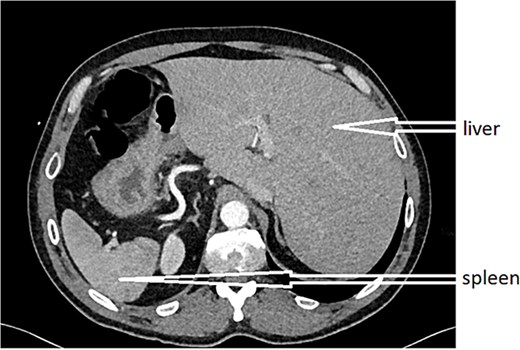

An urgent CT scan revealed situs inversus (Fig. 1) with left-sided high-positioned appendicitis (Fig. 2).

After obtaining informed consent and providing the patient with information about the case, he was transferred to the operating room after preparation, including rehydration, proton pump inhibitor (PPI), antibiotic therapy, and analgesia. Urgent exploratory laparoscopy confirmed the CT findings: retrocecal appendicitis with minimal peritoneal effusion (Fig. 3) in the Douglas pouch. A careful dissection of the appendix from its mesentery was performed, followed by appendectomy (Fig. 4), lavage, and drainage.